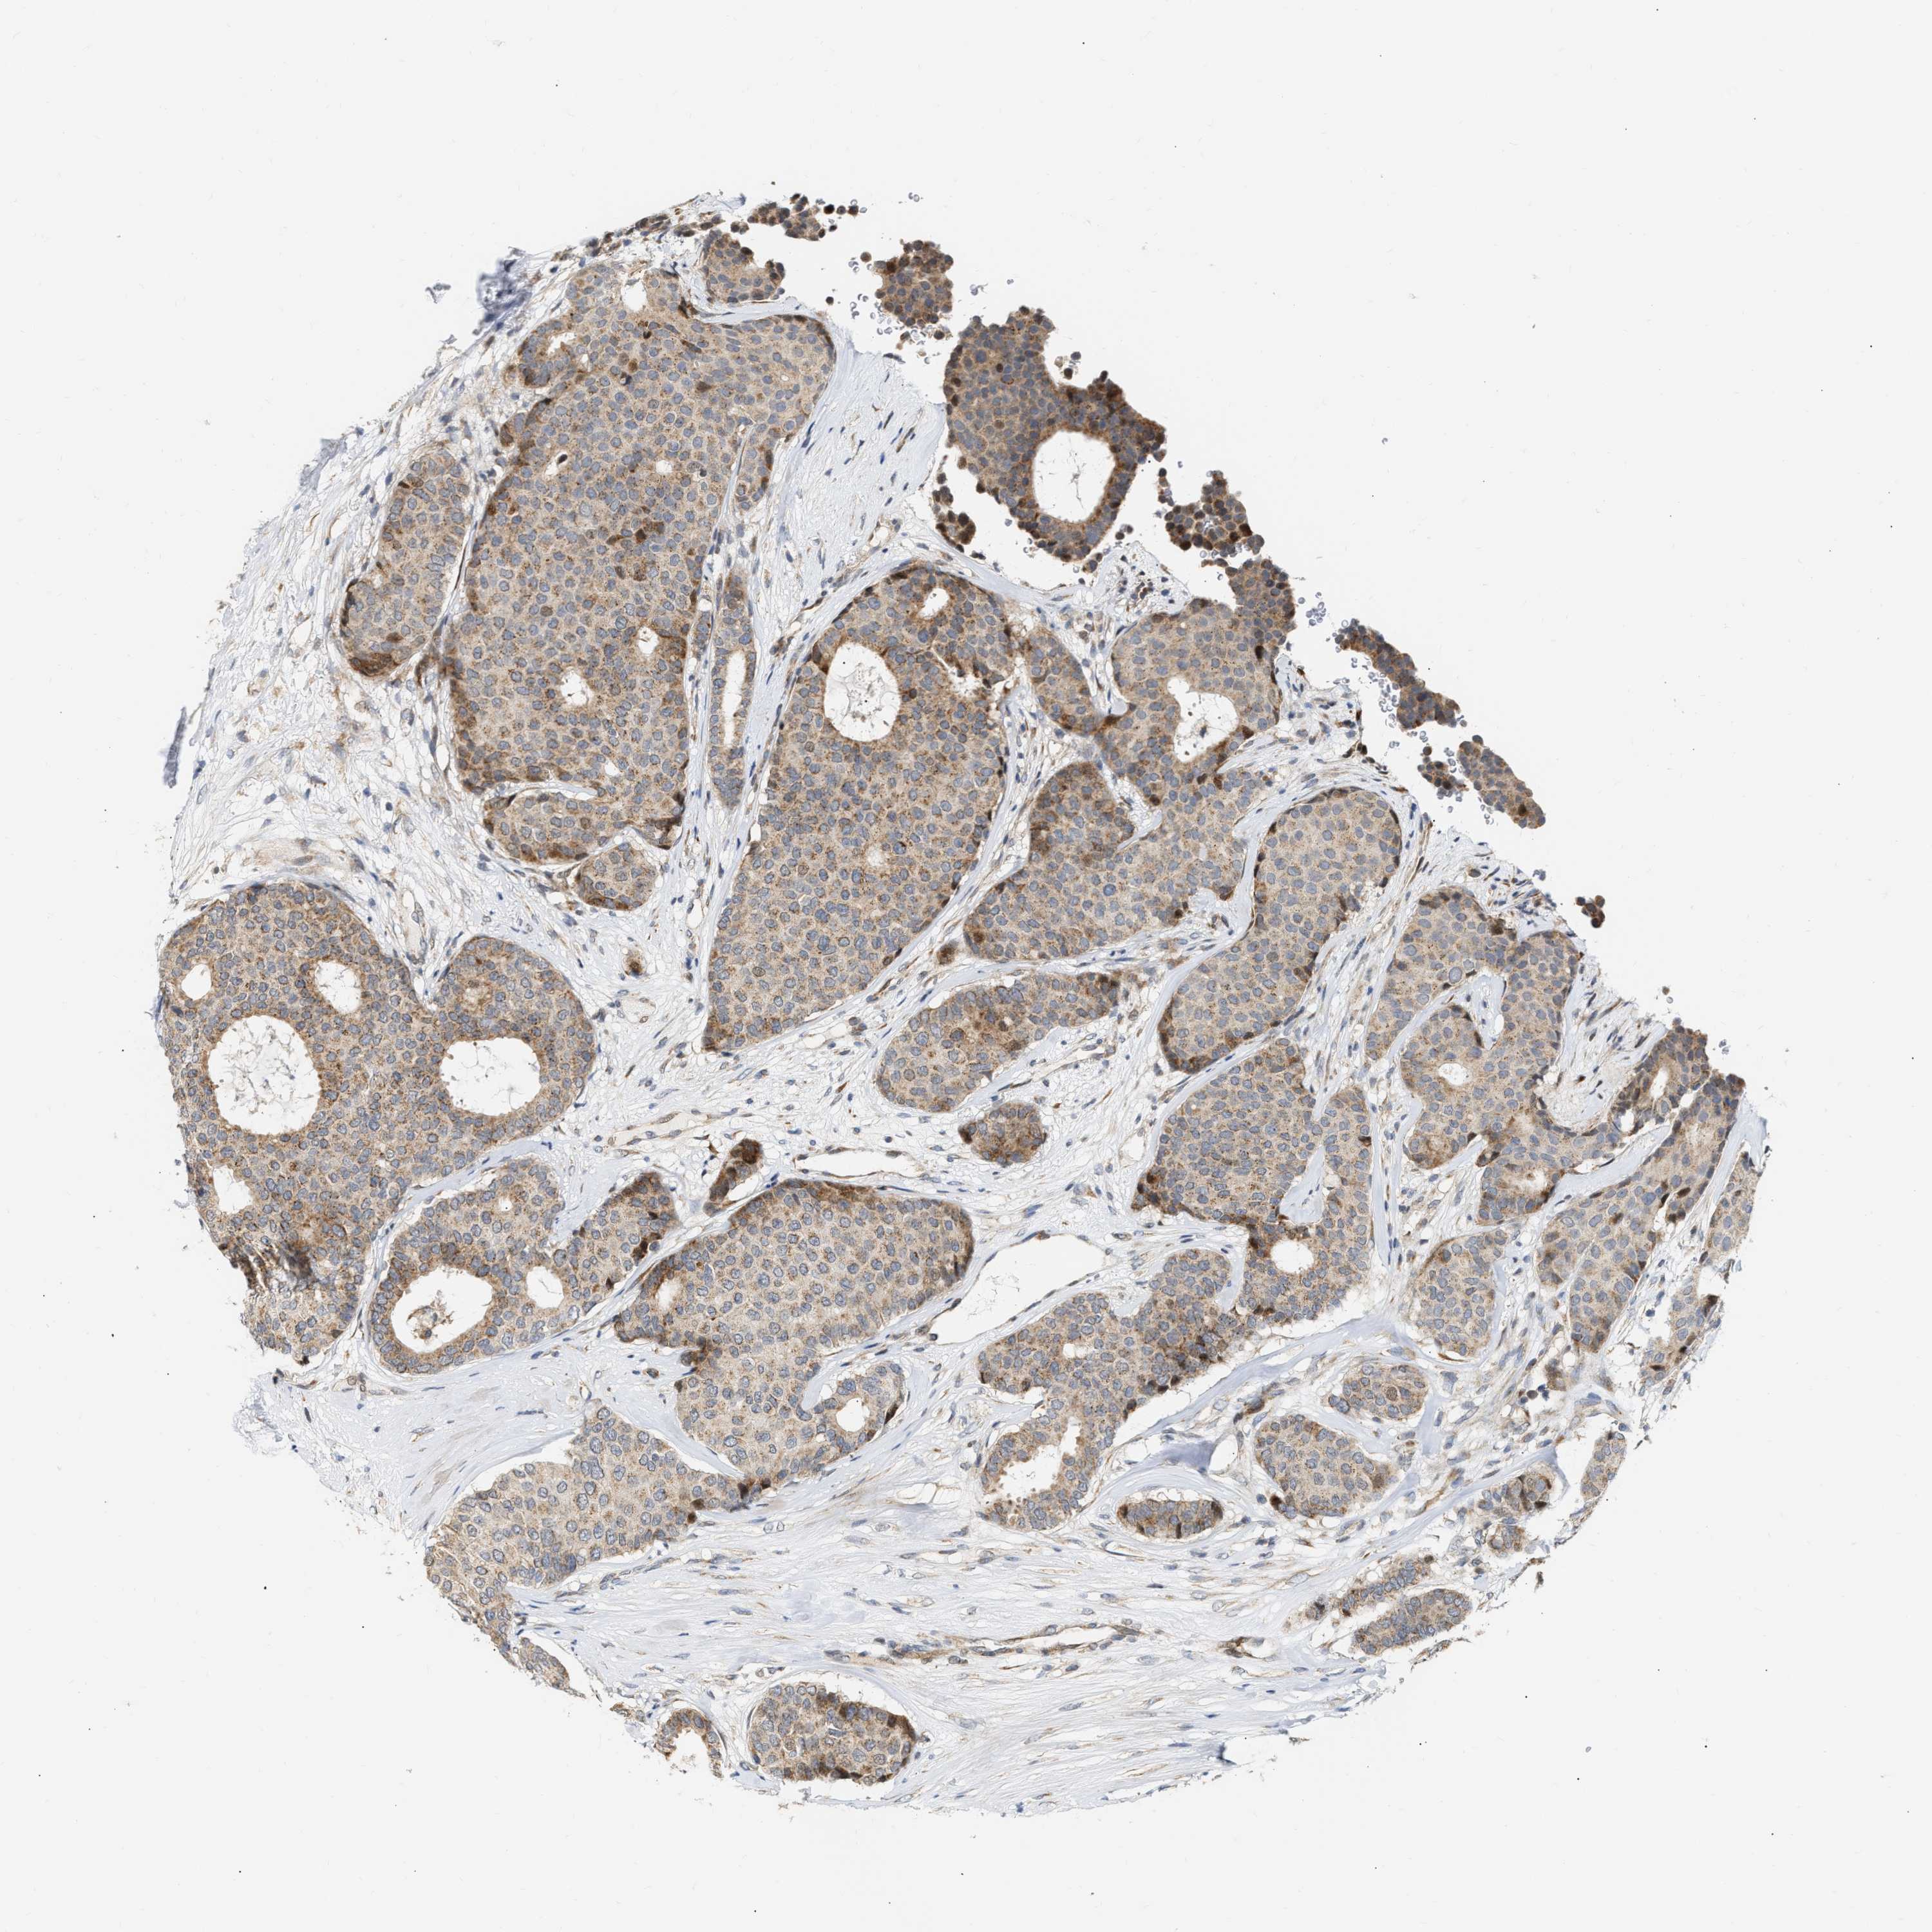

CANCER BREAST CANCER Show tissue menu

BRCA TCGA BRCA VALIDATION PROTEIN EXPRESSION